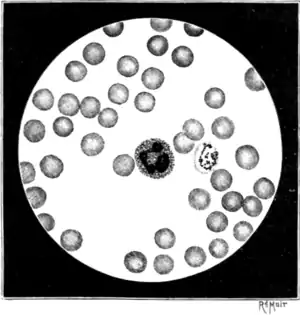

For a thorough appreciation of the principles on which blood examinations for the demonstration and study of the malaria parasite should be conducted, it must be borne in mind that the parasite is intracorpuscular. To see it, therefore, it is necessary, particularly for the beginner, so to dispose the corpuscles in the preparations that a proportion of them shall lie flat on the slide, in a single layer, and presenting their surfaces, and not their edges, to the observer (Fig. 16). It is mainly from ignoring this fundamental principle that so many fail to find the parasite.

On examining successful preparations with the microscope it will be found that the central zone or area contains few or no blood-corpuscles. This zone may be designated the "empty zone." Proceeding outwards from this we come on an area occupied by scattered, isolated, compressed, and much-expanded corpuscles—the "zone of scattered corpuscles." Farther out the corpuscles become more numerous and less expressed (Fig. 16). Gradually, as we trace the film still farther outwards, the corpuscles are found approximated to each other, until, finally, the peripheries of the corpuscles are mostly in touch—the "single-layer zone." Farther out the corpuscles, though still lying flat, are found to overlap each other or are piled one on the top of the other—the "zone of heaped-up corpuscles." Beyond this zone the corpuscles are arranged in rouleaux the "zone of rouleaux." At the extreme margin of the preparation the corpuscles tend to break up and run together so as to form a narrow border of free hæmoglobin, the individual corpuscles perhaps being indistinguishable the "zone of free hæmoglobin." Each of these zones should be studied, for each may afford special information about the malaria parasite.

cent.) and prolonged staining. The stain is dropped on the slip and covered with a watch-glass; after six to eight hours it is washed off with water, the slide dried, and a cover-glass applied with xylol balsam.On examining with a one-twelfth immersion lens slides prepared with methylene blue,[2] the nuclei of the white corpuscles are seen to be very deeply stained, the protoplasm of the white corpuscles is very lightly stained, whilst the parasites are stained an intermediate tint, and show up sharply enough in the faintly tinted red blood-corpuscles (Figs. 2, 16, 20). Contrast staining with eosin is uncertain in its results in methylene-blue preparations; even in practised hands good preparations are the exception. For ordinary purposes I do not recommend it; it is superfluous, troublesome, and unreliable.